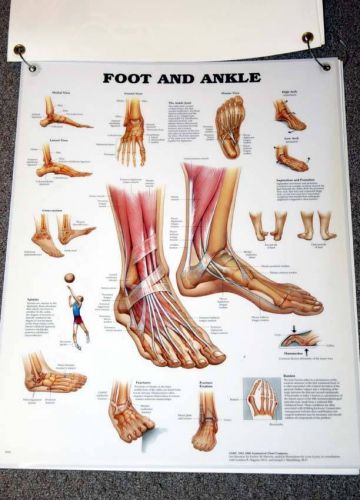

Vintage Large Anatomical Teaching Chart Set Human Skeleton & Foot Podiatry